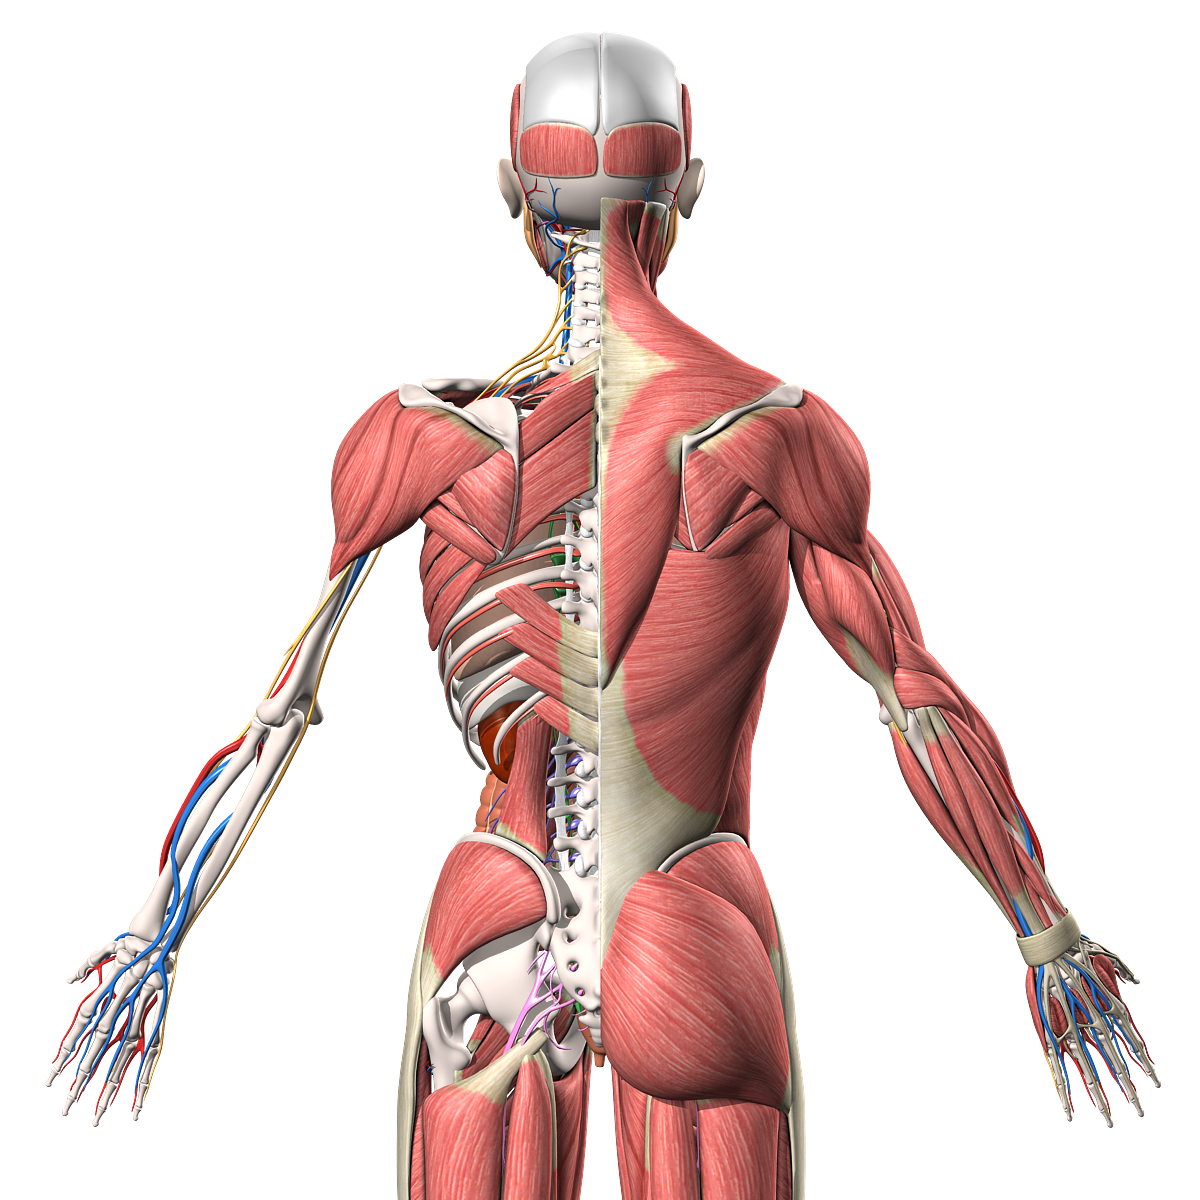

Анатомия человека: кровеносная система и её связь со скелетом